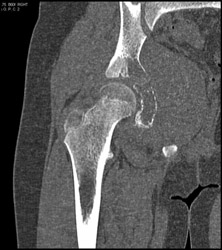

Diagnosis

Tarsal Coalition